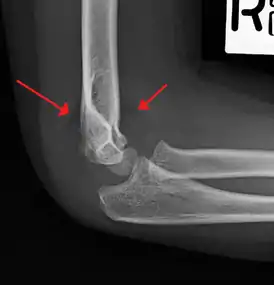

On lateral view of the elbow, there are five radiological features should be looked for: tear drop sign, anterior humeral line, coronoid line, fish-tail sign, and fat pad sign/sail sign (anterior and posterior).[3][8]

Tear drop sign - Tear drop sign is seen on a normal radiograph, but is disturbed in supracondylar fracture.[8]

Anterior humeral line - It is a line drawn down along the front of the humerus on the lateral view and it should pass through the middle third of the capitulum of the humerus.[9] If it passes through the anterior third of the capitulum, it indicates the posterior displacement of distal fragment.[8]

Fat pad sign/sail sign - A non-displaced fracture can be difficult to identify and a fracture line may not be visible on the X-rays. However, the presence of a joint effusion is helpful in identifying a non-displaced fracture. Bleeding from the fracture expands the joint capsule and is visualized on the lateral view as a darker area anteriorly and posteriorly, and is known as the sail sign.[8]

Coronoid line - A line drawn along the anterior border of the coronoid process of the ulna should touch the anterior part of the lateral condyle of the humerus. If lateral condyle appears posterior to this line, it indicates the posterior displacement of lateral condyle.[8]

Fish-tail sign - The distal fragment is rotated away from the proximal fragment, thus the sharp ends of the proximal fragment looks like a shape of a fish-tail.[8]

Anterior and posterior sail sign in a child who has a subtle supracondylar fracture